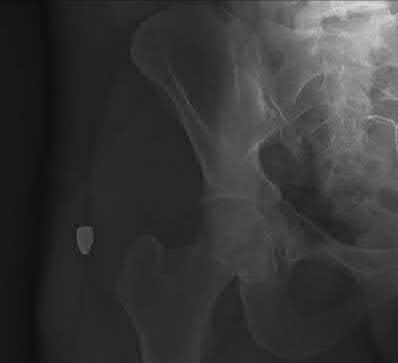

An 82-year-old female presents after a fall at home. Imaging is shown:

She is diagnosed with an unstable intertrochanteric femur fracture. Which of the following anatomic patterns defines an unstable intertrochanteric fracture?

Explanation

Unstable intertrochanteric fracture patterns inherently resist stable reduction and include: reverse obliquity fractures, subtrochanteric extension, large posteromedial comminution (loss of the calcar support), and lateral wall blowout. An intact posteromedial cortex or simple two-part fractures are generally considered stable.